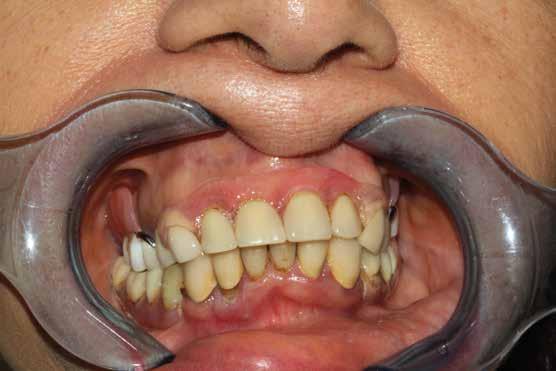

L’esame clinico rappresenta sicuramente la fase di analisi più complessa in quanto i parametri da valutare sono molti e possono interessare tutte le specialità odontoiatriche. Sono da valutare lo stato di salute della dentatura residua, la presenza o meno di manufatti protesici, il rapporto intermascellare,

lo stato di igiene orale, la condizione dei tessuti parodontali, le abrasioni dello smalto che ci indirizzino verso la diagnosi di parafunzioni come il bruxismo, la limitazione nell’apertura della bocca o la presenza di deviazioni per disordini temporo-mandibolari. (Figg. 16-21)

FIG. 17 FIG. 16 FIG. 19 FIG. 18 FIGG. 16-21: Valutazione FIG. 21 FIG. 20